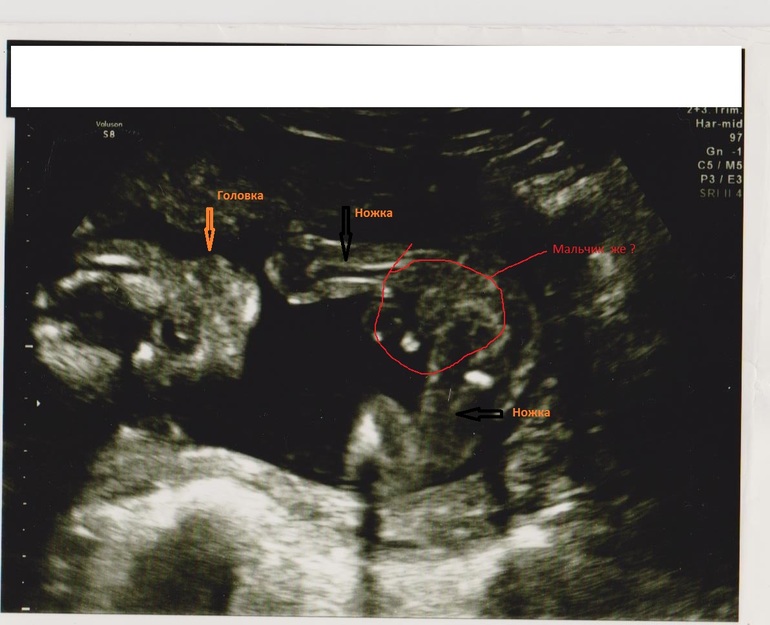

Приветик, девочки, вот нашла ваш сайт и решила зарегистрироваться, тем более есть вопрос : нам сказали пол- МАЛьЧИК. Добавляю фото  Мы очнень рады, но начиталась всего здесь- у нас же точно мальчик, правда ? Спасибо, всем хорошего дня

Мы очнень рады, но начиталась всего здесь- у нас же точно мальчик, правда ? Спасибо, всем хорошего дня